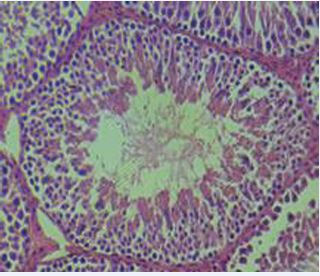

The normal rat testis consists of seminiferous tubules lined by a multilayered spermatogenic epithelium supported by Sertoli cells, surrounded by a thin basement membrane and myoid cells, with interstitial Leydig cells producing testosterone. Spermatogenesis progresses in a cyclical, stage-specific manner that is highly organized and species-characterized [34,35] (Figure 3).

https://www.jscimedcentral.com/public/assets/images/uploads/image-1770639205-1.JPG

Figure 3 Histology of normal testis exhibiting normal germinal epithelium.